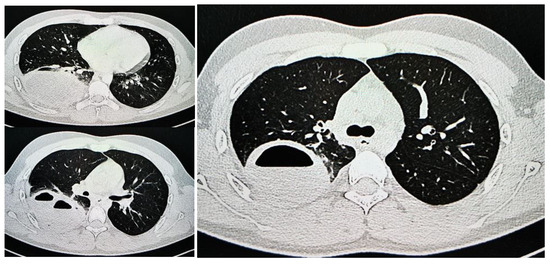

1.9.1. Case 1

1.9.2. Case 2